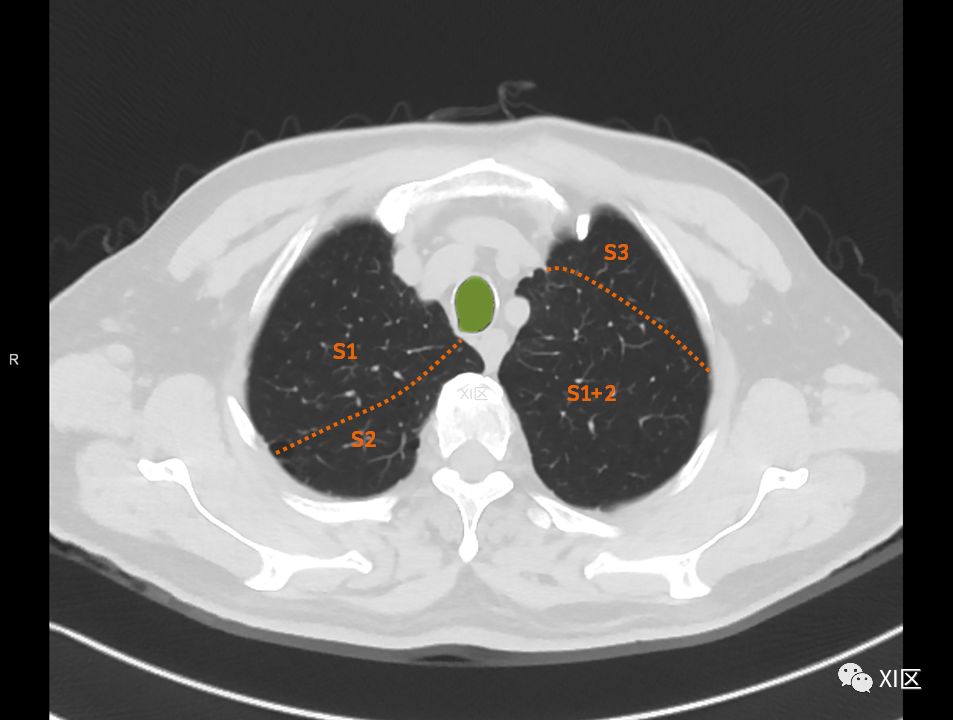

肺的断层分段示意图

在进行肺的分段时,可以上下观察浏览,沿着相应气管的走形可以更容易准确地进行分段。